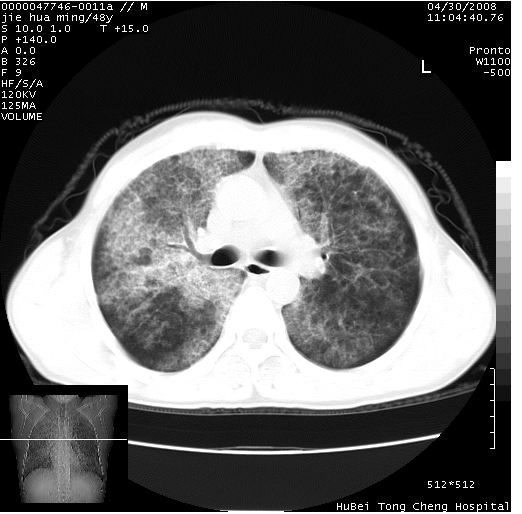

以下是引用dr.yang在2008-5-1 6:25:00的发言:[br]两肺广泛毛玻璃样的片状影,密度不均,边缘欠清,呈碎石路样改变,[br]考虑,1双肺间质性肺炎,2肺泡蛋白沉积症3支气管肺泡癌[br]

以下是引用hhcckk在2008-5-1 8:06:00的发言:[br]支持肺泡蛋白沉积症[br]依据:[br]1、病灶边缘清楚----地图征[br]2、病灶内部小叶间隔或小叶内间隔增厚所形成的网格状影----碎石路样表现[br]3、抗炎治疗无效(炎症抗炎治疗有效)[br]4、纵隔内未见肿大淋巴结(肺泡细胞癌时常有)[br][br]附肺泡蛋白沉积症资料[br][br]肺泡蛋白沉积症(pulmonary alveolar proteinosis)是一种原因不明的以肺泡腔内大量含脂糖蛋白样物质沉积为特征的疾病。[br]病理改变:(1)肺泡和细支气管腔内充满大量含脂糖蛋白样的粘稠物质,该物质为颗粒状或絮状的糖原pas染色阳性的磷脂蛋白。(2)肺泡壁及其间隔无异常改变。胸膜和淋巴结不受累及。(3)晚期可出现弥漫性肺间质纤维化。[br]临床表现:(1)好发年龄30~50岁,男性多于女性,偶见于儿童;(2)主要症状为呼吸困难、咳嗽、低热、消瘦、低氧血症和杵状指等。1/3的患者无症状。(3)实验室检查:痰液或肺泡灌洗液中可找到pas染色阳性颗粒物质。[br]hrct表现:肺泡蛋白沉积症具有特征性改变,即“碎石路样”表现(crazy-paving appearance,cpa)。主要包括(1)斑片状磨玻璃影:指肺野密度朦胧增加,内可见肺血管纹理影,系肺泡腔内充满低密度的磷脂蛋白物质所致。(2)其内部小叶间隔或小叶内间隔增厚所形成的网格状影,为小叶间隔水肿、肺泡壁内淋巴细胞和巨噬细胞浸润以及小叶内淋巴管扩张的缘故。(3)病灶边缘清楚,呈地图样分布于肺野外围或肺门及中央区。[br]

以下是引用zsl6918在2008-5-1 7:35:00的发言:[br]双肺磨玻璃样病变,可见铺碎路石征,病变区与正常区交错。边界清晰。符合肺泡蛋白质沉着征,高分辨扫描会更清楚漂亮。建议临床肺泡灌洗。

以下是引用yangyudong333在2008-5-1 5:36:00的发言:[br][br] 两肺广泛毛玻璃样的片状影,密度不均,边缘欠清,呈碎石路样改变,[br]考虑,1双肺间质性肺炎,2肺泡蛋白沉积症[br]